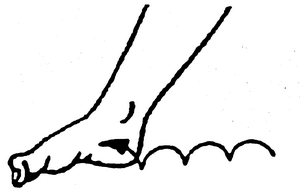

А страсбургский носок

Не дает фасции сильно укоротиться за время сна и тем самым делает вставание на ногу после пробуждения менее болезненным.